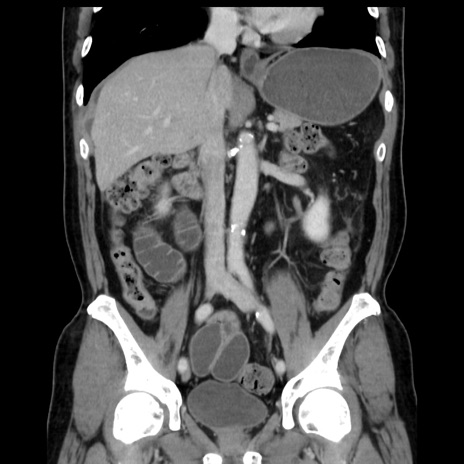

症例16(冠状断像)

【症例】 70歳代男性

【主訴】 腹痛、嘔吐

【現病歴】 約1ヶ月前より間欠的に腹痛と嘔吐あり、当院消化器内科を受診したところCTで多発する肝臓のLDAを指摘され、精査中であった。以降は消化器症状は安定していたが、2日前より嘔気と腹痛があり、同日より排便・排ガスが消失した。改善認めず、 本日、救急外来を受診した。

【既往歴】 大腸ポリープ切除後。

【身体所見】意識清明・会話良好、BT 36.3℃、BP 127/80mmHg、 P 80bpm、腹部:膨満あり、平坦・軟、上腹部正中および下腹部正中に圧痛あり、反跳痛なし、筋性防御なし。

【データ】WBC 7200、CRP 0.77